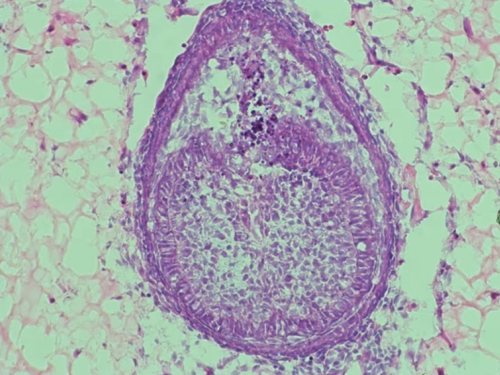

To okruženje, koje znanstvenici nazivaju "skelom", ključno je za uspjeh. U najnovijoj studiji, umjesto kolagena korištenog 2013., tim sada koristi hidrogel, polimer s visokim udjelom vode. "Prvo prikupljamo stanice iz mišjih embrija, zatim ih miješamo i centrifugiramo kako bismo dobili malu staničnu kuglicu. Zatim ubrizgavamo tu kuglicu u hidrogel i uzgajamo je oko osam dana", objasnio je Xuechen Zhang, doktorand na King's Collegeu i koautor studije. Nakon osam dana, unutar hidrogela formiraju se strukture nalik zubima. U prethodnom istraživanju, takvi "zubni zameci" preneseni su u miša gdje su se razvili u zubnu strukturu s korijenom i caklinom.